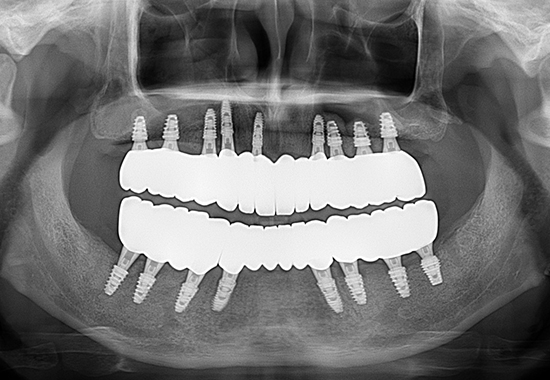

AFTER

- 식립 개수 : 13개 (상악 6개 하악 7개), 크라운 15개

- 수술 내용 : 양쪽상악동 거상